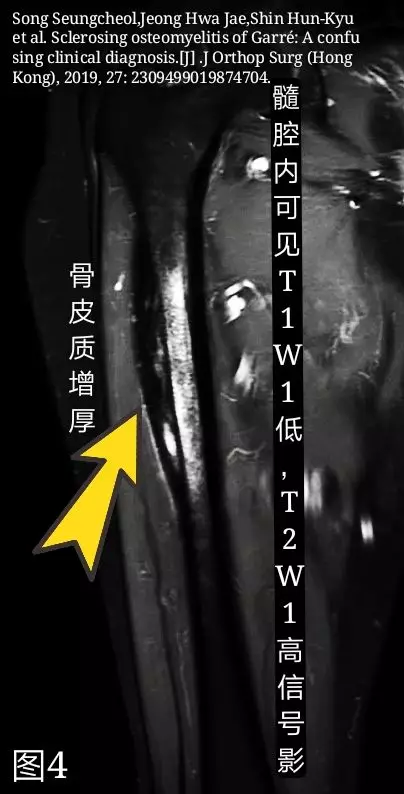

MRI:可见骨皮质明显增厚,胫骨内见T1WI低、T2WI高低混杂信号灶(图4)。